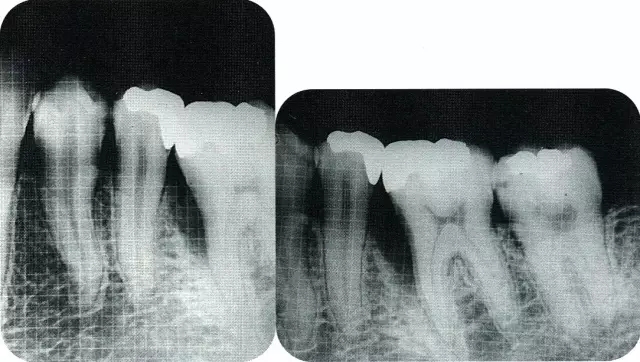

640.webp (8).jpg

▲圖8-2  初診時的x片。尖牙遠(yuǎn)中確認(rèn)有垂直性骨缺損。